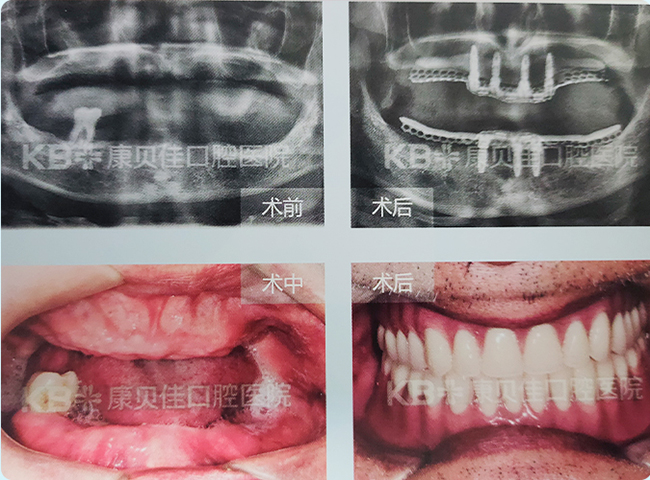

吕女士 64岁

曾在外院就诊被告知难度较大不建议种植,到院检查后发现其上颌、下颌均有牙齿缺失,牙槽骨高度尚可,测量宽度3.9mm,靠近基部倒凹明显,操作难度较大。采用骨劈开术,然后在其上下颌缺牙区各植入2颗植体,恢复8颗牙。

治疗方案:

骨劈开,植入4颗植体,同时植骨盖膜,延期修复。